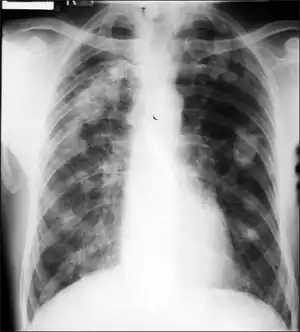

Caplan's syndrome (or Caplan disease or rheumatoid pneumoconiosis[1]) is a combination of rheumatoid arthritis (RA) and pneumoconiosis that manifests as intrapulmonary nodules, which appear homogeneous and well-defined on chest X-ray.[2]

Caplan syndrome is a nodular condition of the lung occurring in dust-exposed persons with either a history of rheumatoid arthritis (RA) or who subsequently develop RA within the following 5–10 years.[3] The nodules in the lung typically occur bilaterally and peripherally, on a background of simple coal workers' pneumoconiosis. There are usually multiple nodules, varying in size from 0.5 to 5.0 cm. The nodules typically appear rapidly, often in only a few weeks. Nodules may grow, remain unchanged in size, resolve, or disappear and then reappear. They can cavitate, calcify, or develop air-fluid levels. Grossly, they can resemble a giant silicotic nodule. Histologically, they usually have a necrotic center surrounded by a zone of plasma cells and lymphocytes, and often with a peripheral inflammatory zone made of macrophages and neutrophils.

Frontal chest radiograph shows Caplan's syndrome.